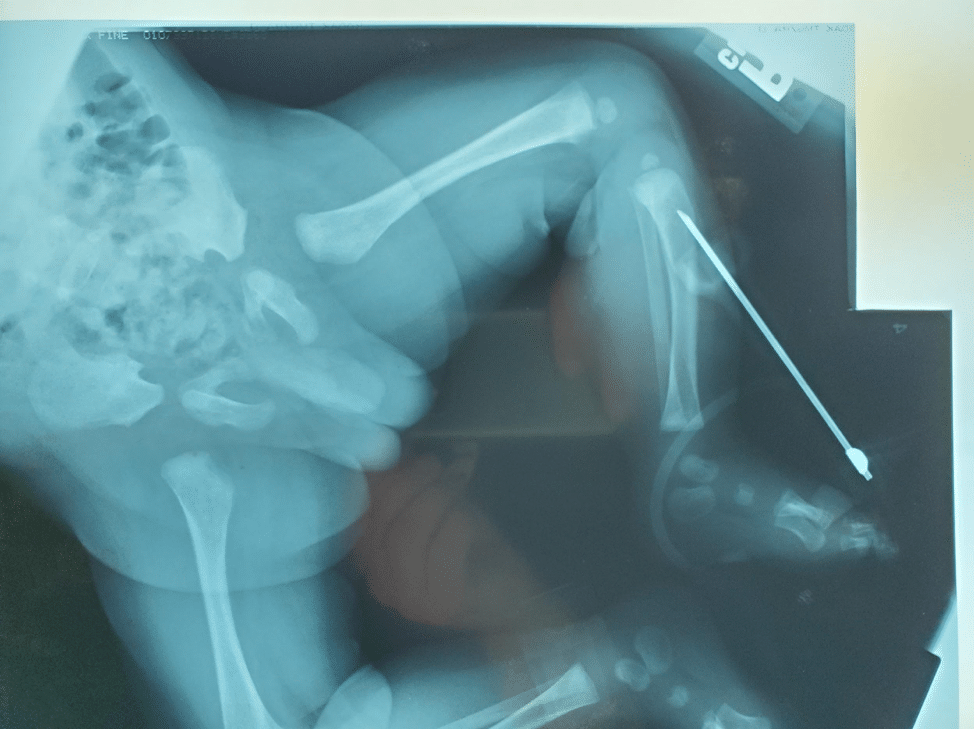

Manual IO insertion. Note the very long needle placed by Mark Dzwonkiewicz FP-C over 25 years ago. Today’s IOs incorporate shorter needles and electric hand-held drills for placement.